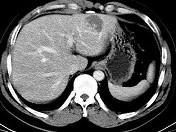

男54岁,B超体检示肝左叶强回声团块影,CT表现如图,最可能的诊断是()A.肝癌B.肝腺瘤C.肝母细胞瘤D.肝血管瘤E.肝脓肿

问题 男54岁,B超体检示肝左叶强回声团块影,CT表现如图,最可能的诊断是()

选项 A.肝癌 B.肝腺瘤 C.肝母细胞瘤 D.肝血管瘤 E.肝脓肿

答案 D